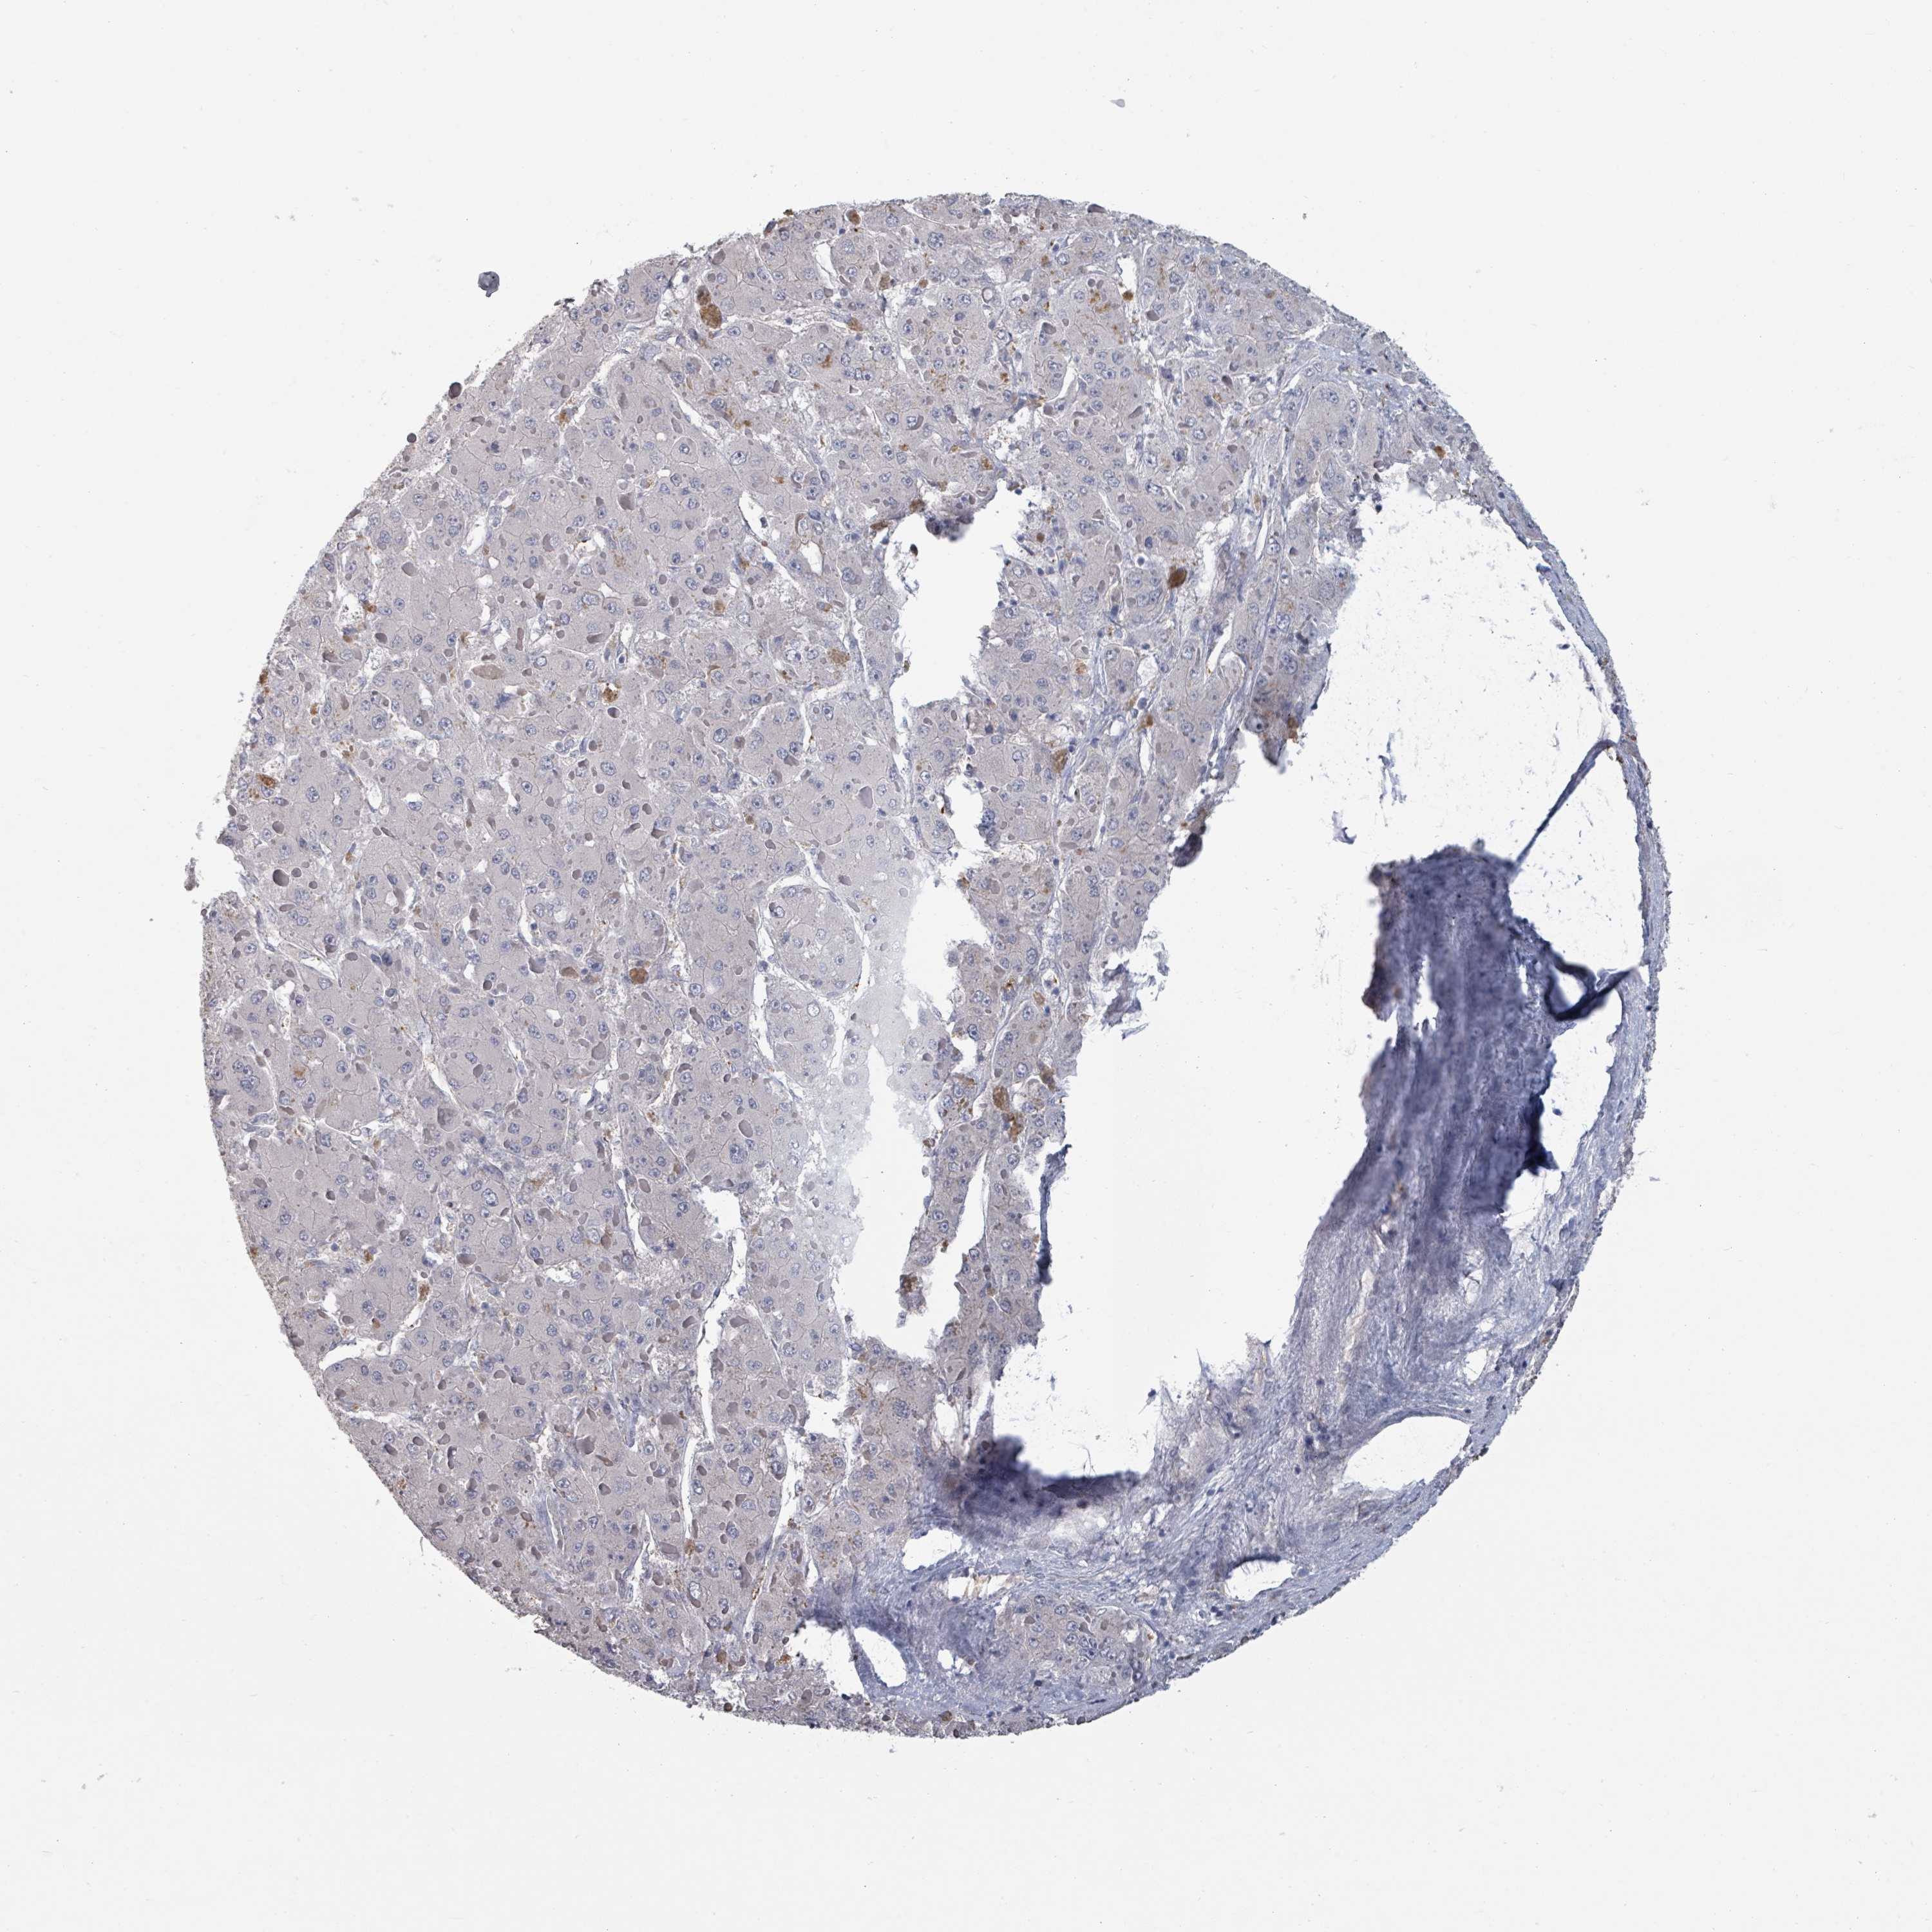

LIVER CANCER - Protein expressioni

A mouse-over function shows sample information and annotation data. Click on an image to view it in a full screen mode. Samples can be filtered based on level of antibody staining by selecting one or several of the following categories: high, medium, low and not detected. The assay and annotation is described here.

Note that samples used for immunohistochemistry by the Human Protein Atlas do not correspond to samples in the TCGA dataset.

Antibody stainingi

Antibody staining in the annotated cell types in the current human tissue is reported as not detected, low, medium, or high, based on conventional immunohistochemistry profiling in selected tissues. This score is based on the combination of the staining intensity and fraction of stained cells.

Each image is clickable and will lead to virtual microscopy that enables deeper exploration of all samples and also displays staining intensity scores, fraction scores and subcellular localization as well as patient and tissue information for each sample.

Antibody HPA050843

Staining

High

Medium

Low

Not detected

Intensity

Strong

Moderate

Weak

Negative

Quantity

>75%

75%-25%

<25%

None

Location

Nuclear

Cytoplasmic/membranous

Cytoplasmic/membranous,nuclear

Carcinoma, Hepatocellular, NOS